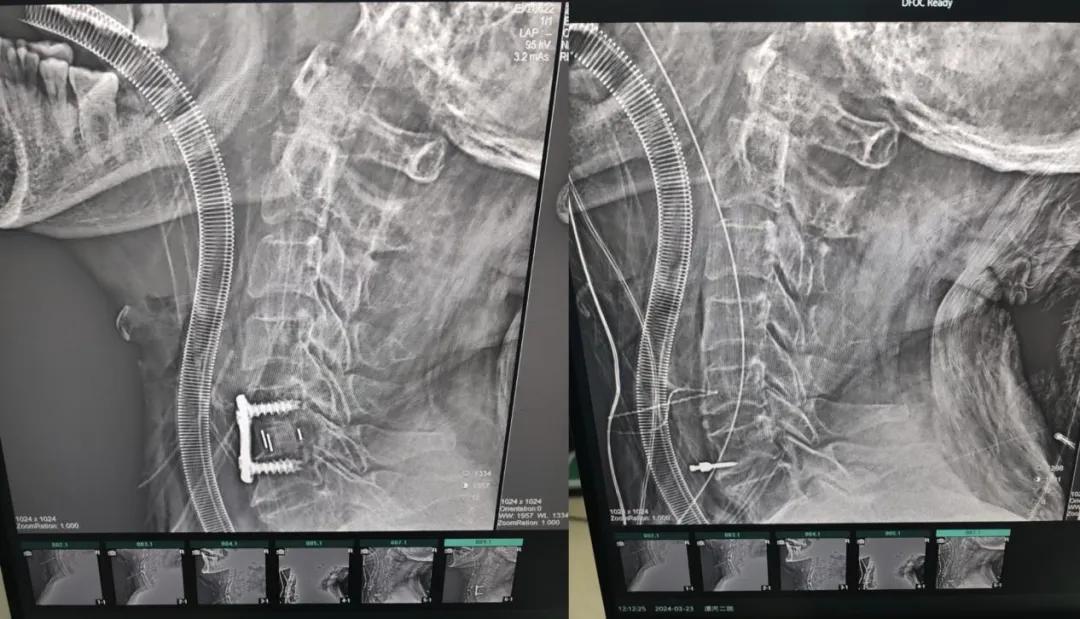

近日,70歲的馬阿姨,因摔傷后出現(xiàn)持續(xù)性頸部疼痛伴右側(cè)肢體無力、麻痛,影響日常生活。于是來到市二院神經(jīng)外科就診,經(jīng)檢查發(fā)現(xiàn):頸椎MR示:頸3/4、4/5、5/6、6/7椎間盤變性突出(中央型)并繼發(fā)性椎管變窄,頸椎退行性改變,頸5椎體水平頸髓水腫。神經(jīng)外科副主任劉沛濤根據(jù)患者癥狀、體征、影像學(xué)三者結(jié)合診斷為“脊髓型頸椎病”,考慮到患者癥狀逐漸加重、保守治療效果不佳等情況,建議盡快手術(shù)治療。

經(jīng)過縝密的術(shù)前準(zhǔn)備和手術(shù)計劃,在鄭大一附院神經(jīng)外科張風(fēng)江教授的指導(dǎo)下,神經(jīng)外科團(tuán)隊順利為患者實(shí)施“顯微鏡下頸椎前路C5/C6椎間盤切除椎間融合+內(nèi)固定術(shù)”,手術(shù)時間不到1小時。術(shù)后患者恢復(fù)情況良好。